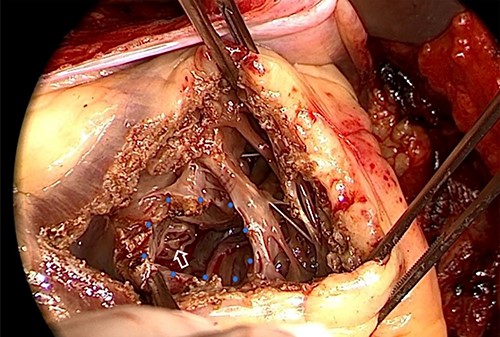

After receiving informed consent, surgery was performed as patch closure of ruptured VSA and coronary artery bypass grafting (CABG) under cardiopulmonary bypass (CPB) on the 11th day after admission. Median sternotomy was done to establish a CPB by the ascending aorta and bicaval cannulation, and right supra-pulmonary venous venting was added. Cardiac arrest was obtained by cold blood cardioplegia via the coronary sinus with intermittent delivery to maintain cardiac standstill. In the surgical findings, VSA was noted at the center of the ventricular septum with circular wall defect of ~15 mm on the RV side (Fig. 3). A part of the perforated myocardium in the aneurysm was resected for histopathologic examination. After the defective edge of the VSA was carefully trimmed, it was closed by extended sandwich patch technique using the double Polyester patch. CABG was added on the left anterior descending artery using left internal thoracic artery and right coronary artery using the right greater saphenous vein.

VSA at the center of ventricular septum (blue dot circle) with VSP to the RV cavity (white arrow) in the operative finding. VSA: ventricular septal aneurysm, VSP: ventricular septal perforation, RV: right ventricle.